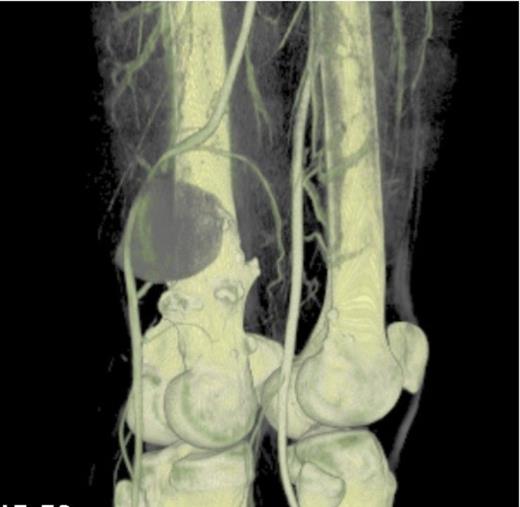

An ultrasound concluded an 8.8cm pseudoaneurysm and the patient was admitted for urgent pre-op CT angio (figure 3 and 4) and surgical exploration.

CT angiogram 3D reconstruction- Showing the bony exostoses and the popliteal aneurysm posterior to the right distal femur